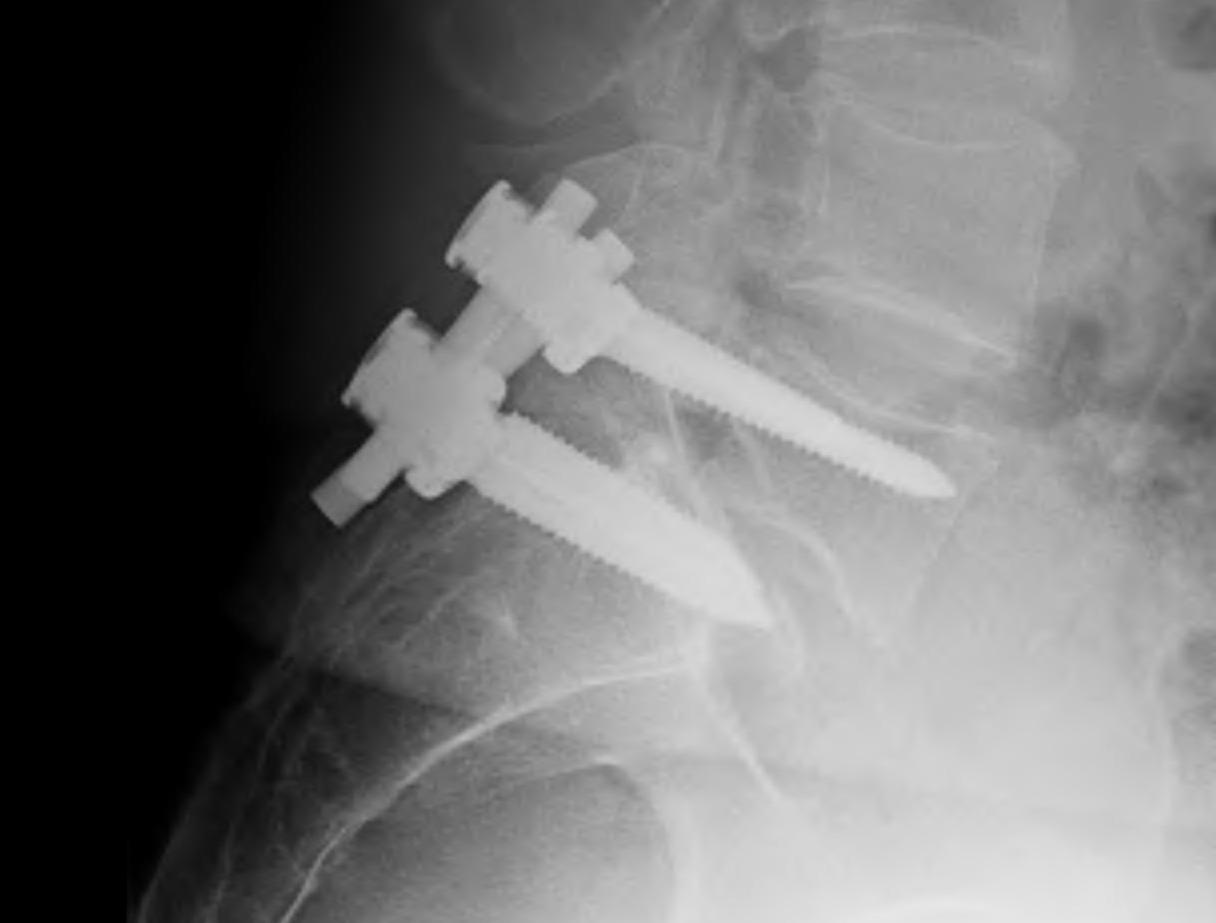

Reduction + Instrumented fusion

Indications

- sagittal malignment

Disadvantage

- risk of neurology (L5)

- up to 25%, usually transient

Advantage

- cosmesis

- less pain from correction of alignment

- more likely fusion, less pseuodoarthrosis

- improved neurological decompression

Technique

A. Posterior approach

- wide foraminatomy bilateral to protect L5 nerve root

- disc removed

- screws used to correct angulation +/- some translation

- interbody fusion device to restore height

B. Anterior approach